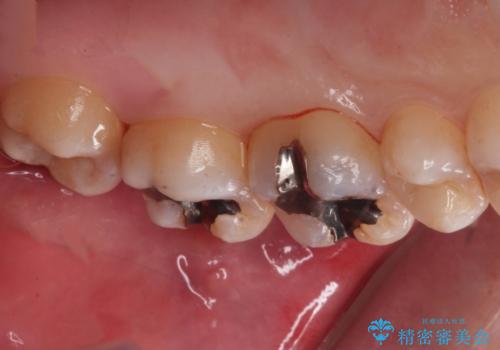

縁下歯石のクリーニングの症例写真

縁下歯石のクリーニング

1. 縁下歯石のクリーニングの治療前